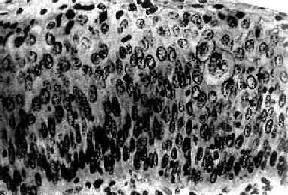

图13-3 子宫颈原位癌 癌变限于上皮层内,细胞核肥大、深染,大小不一,形态不规则,核仁明显,核分裂像易见,且见巨细胞(右侧上方),这种细胞间变累及上皮全层,但基底膜完整,癌细胞未浸润到基底膜下间质 由于重度不典型增生和原位癌没有明显界限,有学者将不同程度的不典型增生和原位癌统称为宫颈上皮内新生物(cervical intraepithelial neoplasm,CIN)。Ⅰ级(轻度)不典型增生为CINⅠ。Ⅱ级(中度)不典型增生为CINⅡ。Ⅲ级(重度)不典型增生及原位癌为CINⅢ。他们认为这些病变是有连续关系的,只是在程度上不同而已。这一组病变是处于正常鳞状上皮和浸润癌之间的变化阶段。上皮的不典型增生-原位癌-浸润癌是一个逐渐连续发展的过程。但并非所有子宫颈浸润癌的形成均必须通过这一过程,也不是所有的上皮不典型增生均必然发展为子宫颈癌。癌前病变具有进展性和可逆性,决定于病变的范围及程度。

三、子宫颈原位癌子宫颈原位癌(carcinoma in situ)癌细胞局限于上皮全层内、尚未穿破上皮基底膜侵入下方固有膜。子宫颈原位癌的异型细胞比不典型增生者更具显着的多形性。镜下,上皮层完全为癌细胞所取代,细胞大小、形状不一,呈圆形、卵圆形、梭形,偶见巨核、多核,排列紊乱,层次不清,极向消失。核大浓染、大小及形状不一、染色质增粗,核分裂像常见,并有病理性核分裂像。胞浆相对减少,核浆比值增大(图13-3)。原位癌癌细胞可由表面沿基底膜伸入腺体内,致整个腺管或其一部分为癌细胞所取代,但腺管轮廓尚存,腺体基底膜完整,癌细胞未浸润到固有膜。这种变化称原位癌累及腺体。原位癌累及腺体并不一定发展为浸润癌。部分子宫颈原位癌可长期不发生浸润,个别病例甚至可自行消退。但由于原位癌特别是原位癌累及腺体具有发展为浸润癌的倾向,故一旦发现,应及时给予适当治疗。